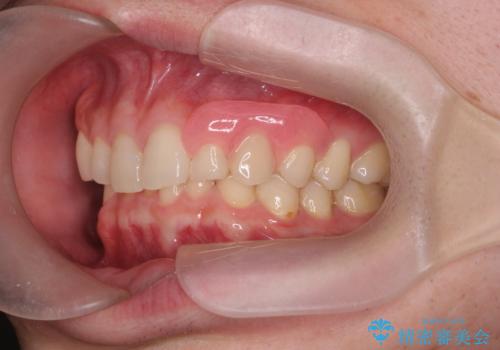

型取りと装着の2回で治療を終了することができました。

- ブリッジやインプラントと比較して、色が合いづらい、見た目の違和感があります

- ブリッジやインプラントと比較して、話しにくい、舌が当たる等の違和感があります